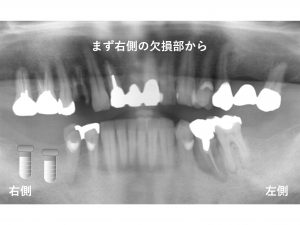

以下が初診時です。

下顎の右側奥歯が2歯欠損、

下顎左側の奥歯が1歯欠損しています。

さらに

上顎右側奥から4番目の歯と

下顎左側奥から2番目の歯が

歯根破折 しています。

これらの歯根破折 している歯は、

抜歯 しか方法はありませんでした。

下顎右側の欠損部から

インプラント治療を開始することにしました。